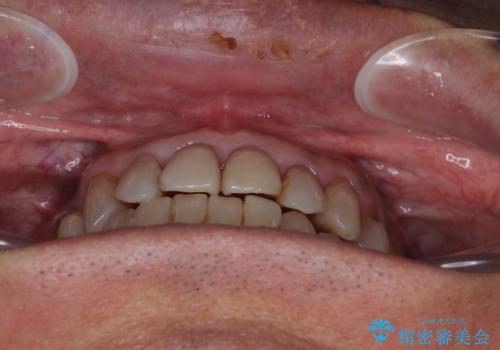

今からでも綺麗な歯並びを手に入れたい 40代男性のワイヤー矯正

- 前歯のクロスバイトを気にして来院された患者様です。

40代男性で、インプラント補綴治療も経験されている方で、矯正治療をしても良いのかと悩んでいらっしゃいました。

下顎骨の左右のずれがあり、下顎全体が前方に出ている状態であったので、無理をせずにワイヤー装置にて矯正治療を行うこととしました。

クロスバイト改善には難儀しましたが、咬みやすく、笑ったときに清潔感ある口元に仕上げることができました。